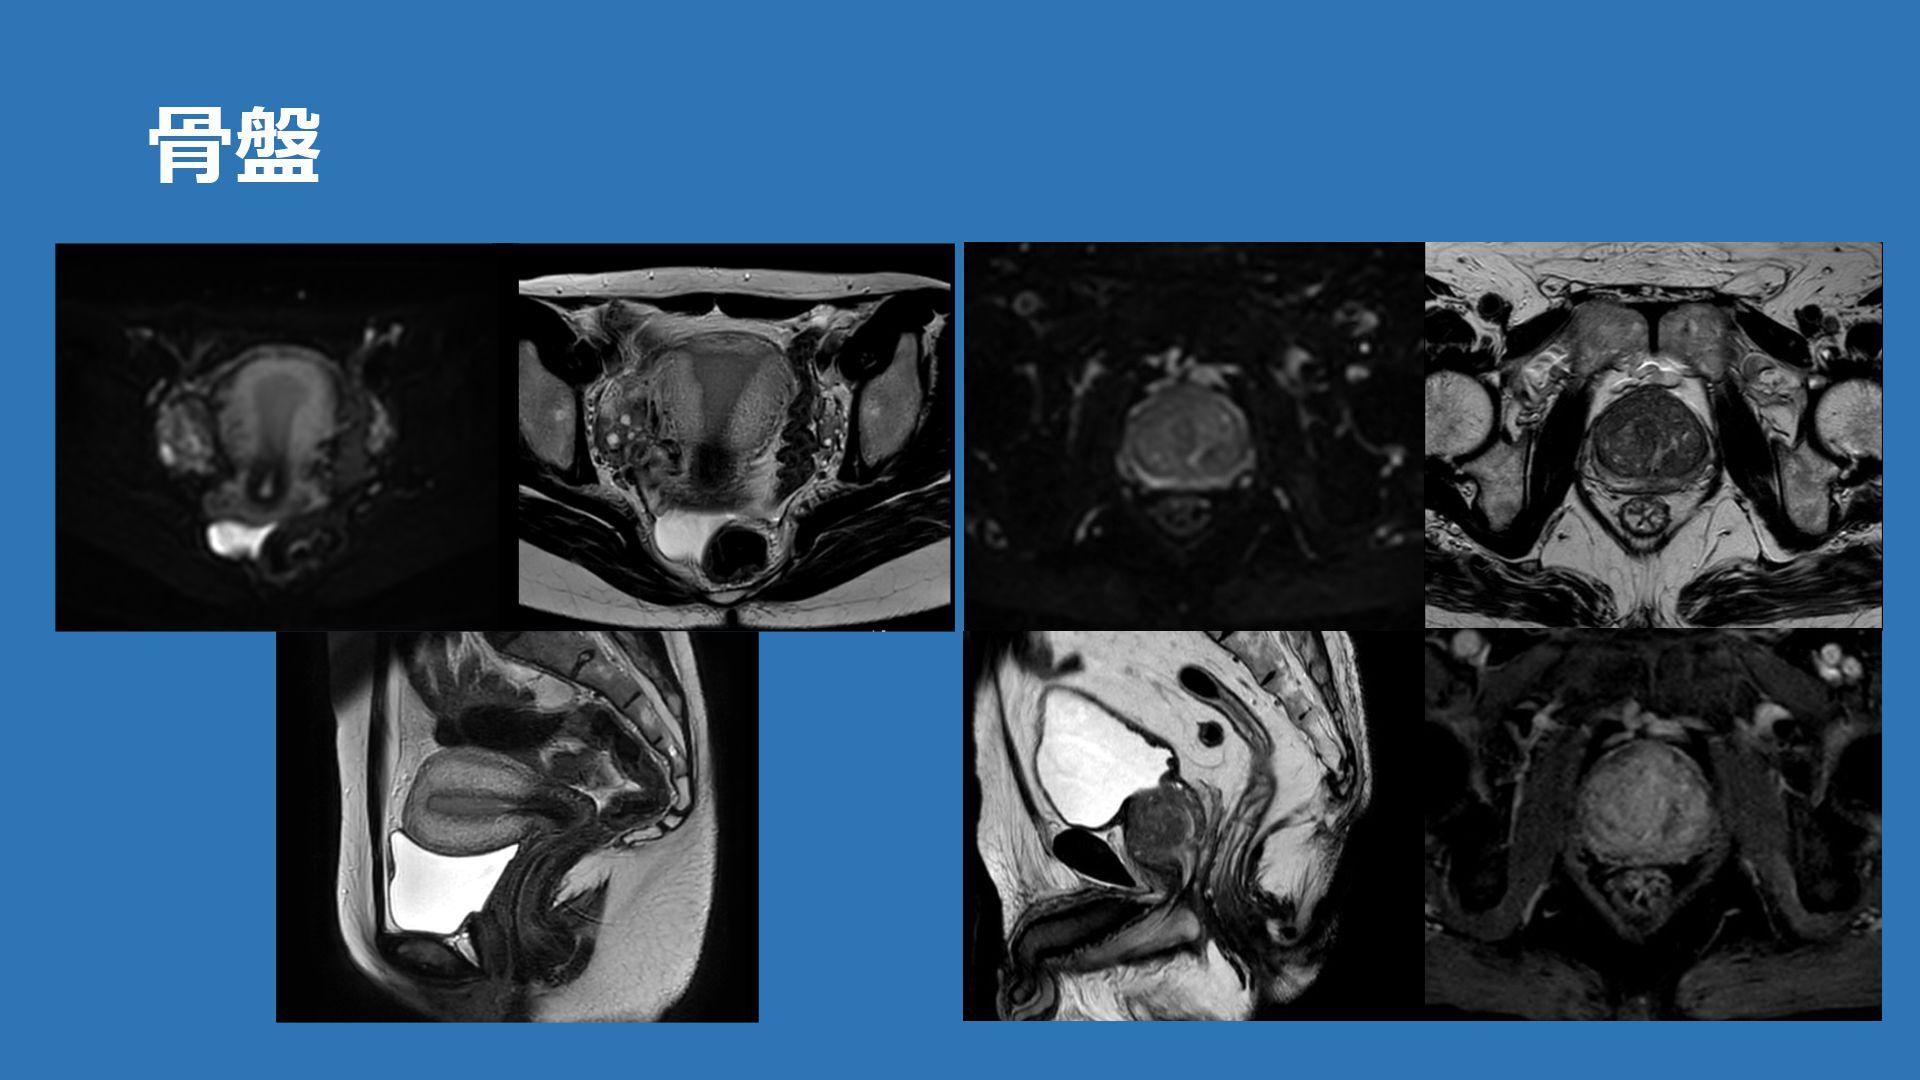

⾻盤